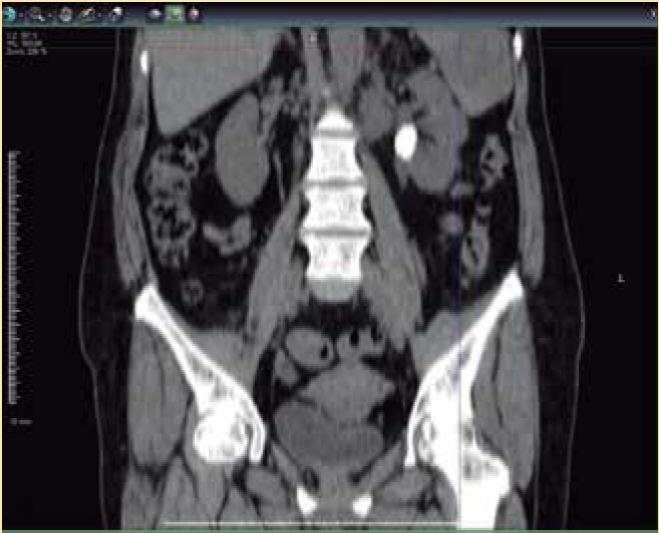

Se solicitaron exámenes paraclínicos de laboratorio completos que demostraron la presencia de leucocitosis a expensas de neutrofilia, con eritrocitos incontables por campo y cristales de oxalato de calcio regulares en el examen general de orina, con calcio sérico y niveles de paratohormona dentro de rangos normales. Se realizó una radiografía simple de abdomen que demostró la presencia de una imagen radiopaca. Dados los hallazgos se efectuó una urotomografía (UROTAC), y se apreció en el topograma una imagen redondeada radiopaca a nivel paravertebral izquierdo de L1 a L2 (Figura 1). En los cortes axial, coronal y en la reconstrucción tridimensional en fase simple y contrastada se hizo evidente una imagen hiperdensa en la pelvis renal izquierda con dimensiones de 2.19 × 1.54 × 2.58 cm e índice de atenuación de hasta 1762 unidades Hounsfield (Figura 2 3, 4), y se hizo el diagnóstico de litiasis piélica izquierda. Se inició impregnación antibiótica empírica previa toma de urocultivo y posteriormente se indicó tratamiento quirúrgico por medio de pielolitotomía laparoscópica izquierda. La evolución fue adecuada en el periodo postoperatorio. La paciente egresó al tercer día del postquirúrgico. Actualmente se encuentra en manejo multidisciplinario por endocrinología y urología, en espera del perfil metabólico para su adecuada categorización y tratamiento postevento lítico.

Figura 2 Urotomografía en fase simple y corte axial: imagen hiperdensa en la pelvis renal izquierda.